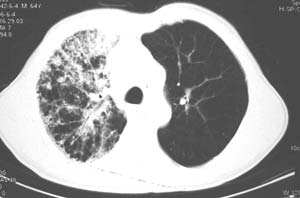

右肺上叶大片片状、网格状及索条致密影,前半部密实向后逐渐疏松,其内参杂斑点状小结节,密度不均匀,内见含气支气管像,纵隔内见肿大淋巴结,其他肺呈弥漫性小叶中心性性肺气肿改变,结合男 64  咳血,咳痰,发热3天,血象1.2万。考虑:1 慢性支气管炎、肺气肿合并右上肺感染。2 不除外结核合并感染的可能。

右肺上叶见片状 网格状及索条致密影.其内参杂斑点状小结节,部分融合,密度不均匀,内见含气支气管像,前段有一小片结影,纵隔内见肿大淋巴结,右侧胸腔少量积液。.结合男 64  咳血,咳痰 发热 3天 血象1.2万,综合考虑:2 右上肺感染伴间质纤维化 2 警惕细支气管肺泡癌。3建议结合临床及进一步检查[痰及纤支镜]或治疗后复查

右侧胸阔塌陷,纵隔右移。右上肺大片状高密度影,沿支气管血管束走行,内见点状钙化;支气管充气征阳性,支气管呈柱状扩张;胸膜下小叶间隔增厚;右侧后胸壁内侧见带状水样密度影;纵隔淋巴结增大。

影像学表现:右肺上叶大片状、网格状及索条致密影,前半部密实向后逐渐疏松,其内参杂斑点状小结节,密度不均匀,内见含气支气管像,纵隔内见肿大淋巴结.